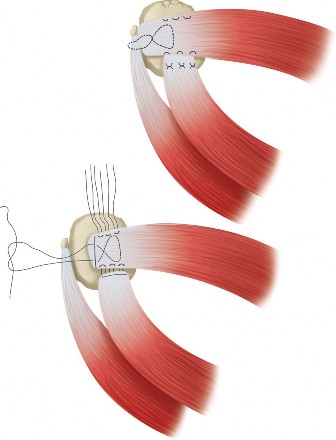

The correct answer is (A). Massive and immobile tears can be either U-shaped or longitudinal. These can sometimes be repaired using an anterior or posterior

interval slide technique. In an anterior interval slide technique, there is some anterior portion of the supraspinatus still attached to the greater tuberosity laterally and rotator interval anteriorly. The greater tuberosity attachment can be incised and the rotator interval attachment can be detached by incising the coracohumeral ligament. In a posterior interval slide technique, there is some posterior portion of the supraspinatus still attached to the infraspinatus. This can be detached by incising the interval between the supraspinatus and infraspinatus (Answer B). These interval slide techniques decrease the tension and improve lateral mobilization, allowing the supraspinatus to be more easily repaired to the greater tuberosity. The posterior leaf of the tear is then brought together with the anterior leaf through marginal convergence, leaving you with a small crescent-shaped tear that can be repaired to the greater tuberosity (see Fig. 2–16).

Figure 2–16_Massive, immobile rotator cuff tear and repair using anterior interval slide followed by marginal convergence. SS, supraspinatus; IS/TM, infraspinatus/teres minor; RI, rotator interval; CHL, coracohumeral ligament; Sub, subscapularis. (Redrawn from Burkhart SS, Lo IKY. Arthroscopic rotator cuff repair. J _Am Acad Orthop Surg. 2006;14(6):333–346.)

Crescent-shaped tears are not retracted much medially, can be mobilized laterally relatively easily, and thus can be relatively easily repaired to humeral bone (see Fig. 2–13).

Figure 2–13_Crescent-shaped rotator cuff tear and repair. SS, supraspinatus; IS, infraspinatus. (Redrawn from Burkhart SS, Lo IKY. Arthroscopic rotator cuff repair. _J Am Acad Orthop Surg. 2006;14(6):333–346.)

U-shaped tears can be repaired using marginal convergence (Answer E). U-

shaped tears have an apex that extends further medially, usually to the edge of the glenoid in the sagittal plane, and this part cannot be mobilized all the way to the greater tuberosity. Because of this lack of mobility, these tears have to be repaired using marginal convergence, which is essentially zipping up the U from the apex toward the greater tuberosity using side to side sutures to bring together the anterior and posterior leaves of the U-shaped tear. In performing this marginal convergence, you essentially are converting a U-shaped tear into a crescent-shaped tear that can be relatively easily mobilized to the greater tuberosity, allowing it to be repaired (see Fig. 2–14).

Figure 2–14_U-shaped rotator cuff tear and repair using marginal convergence. SS, supraspinatus; IS, infraspinatus. (Redrawn from Burkhart SS, Lo IKY. Arthroscopic rotator cuff repair. _J Am Acad Orthop Surg. 2006;14(6):333–346.)

Finally, an L-shaped tear resembles a tear that can be thought of as partially a crescent-shaped tear and partially a U-shaped tear. One leg of the L is the more mobile, less retracted, crescent-shaped tear which transitions into the other leg of the L, a less mobile, more retracted part of the tear which mechanically and visually resembles a U-shaped tear. The retracted U-shaped part, like a normal U-shaped tear, must be repaired using marginal convergence. Then the remaining crescent-shaped part, like a normal crescent-shaped tear, can be mobilized laterally and repaired to bone (see Fig. 2–15).

Figure 2–15_L-shaped rotator cuff tear and repair using marginal convergence. SS, supraspinatus; IS, infraspinatus; RI, rotator interval; CHL, coracohumeral ligament; Sub, subscapularis. (Redrawn from Burkhart SS, Lo IKY. Arthroscopic rotator cuff repair. _J Am Acad Orthop Surg. 2006;14(6):333–346.)